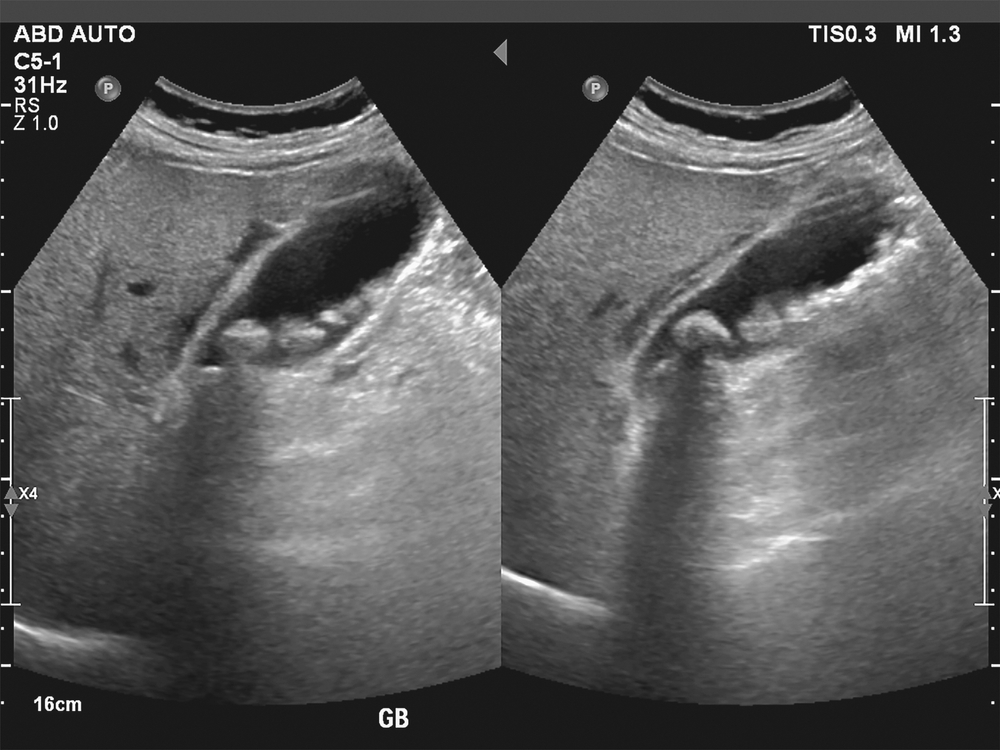

Фотогалерея

Оборудование УЗИ